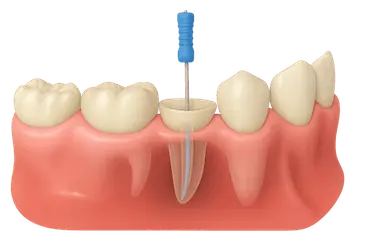

Acceso al nervio dental: apertura del diente para tratar la infección

Una vez anestesiado el diente, el odontólogo realiza una pequeña apertura en la corona para acceder al interior de la pieza.

A través de ese punto se llega al conducto radicular, donde se encuentra el nervio afectado.

Con instrumentos muy finos y controlados, se retira la pulpa dañada para detener la infección y aliviar la presión que causa el dolor.

Este paso permite acceder con precisión al interior del diente y preparar la zona para la limpieza profunda que se realiza a continuación.